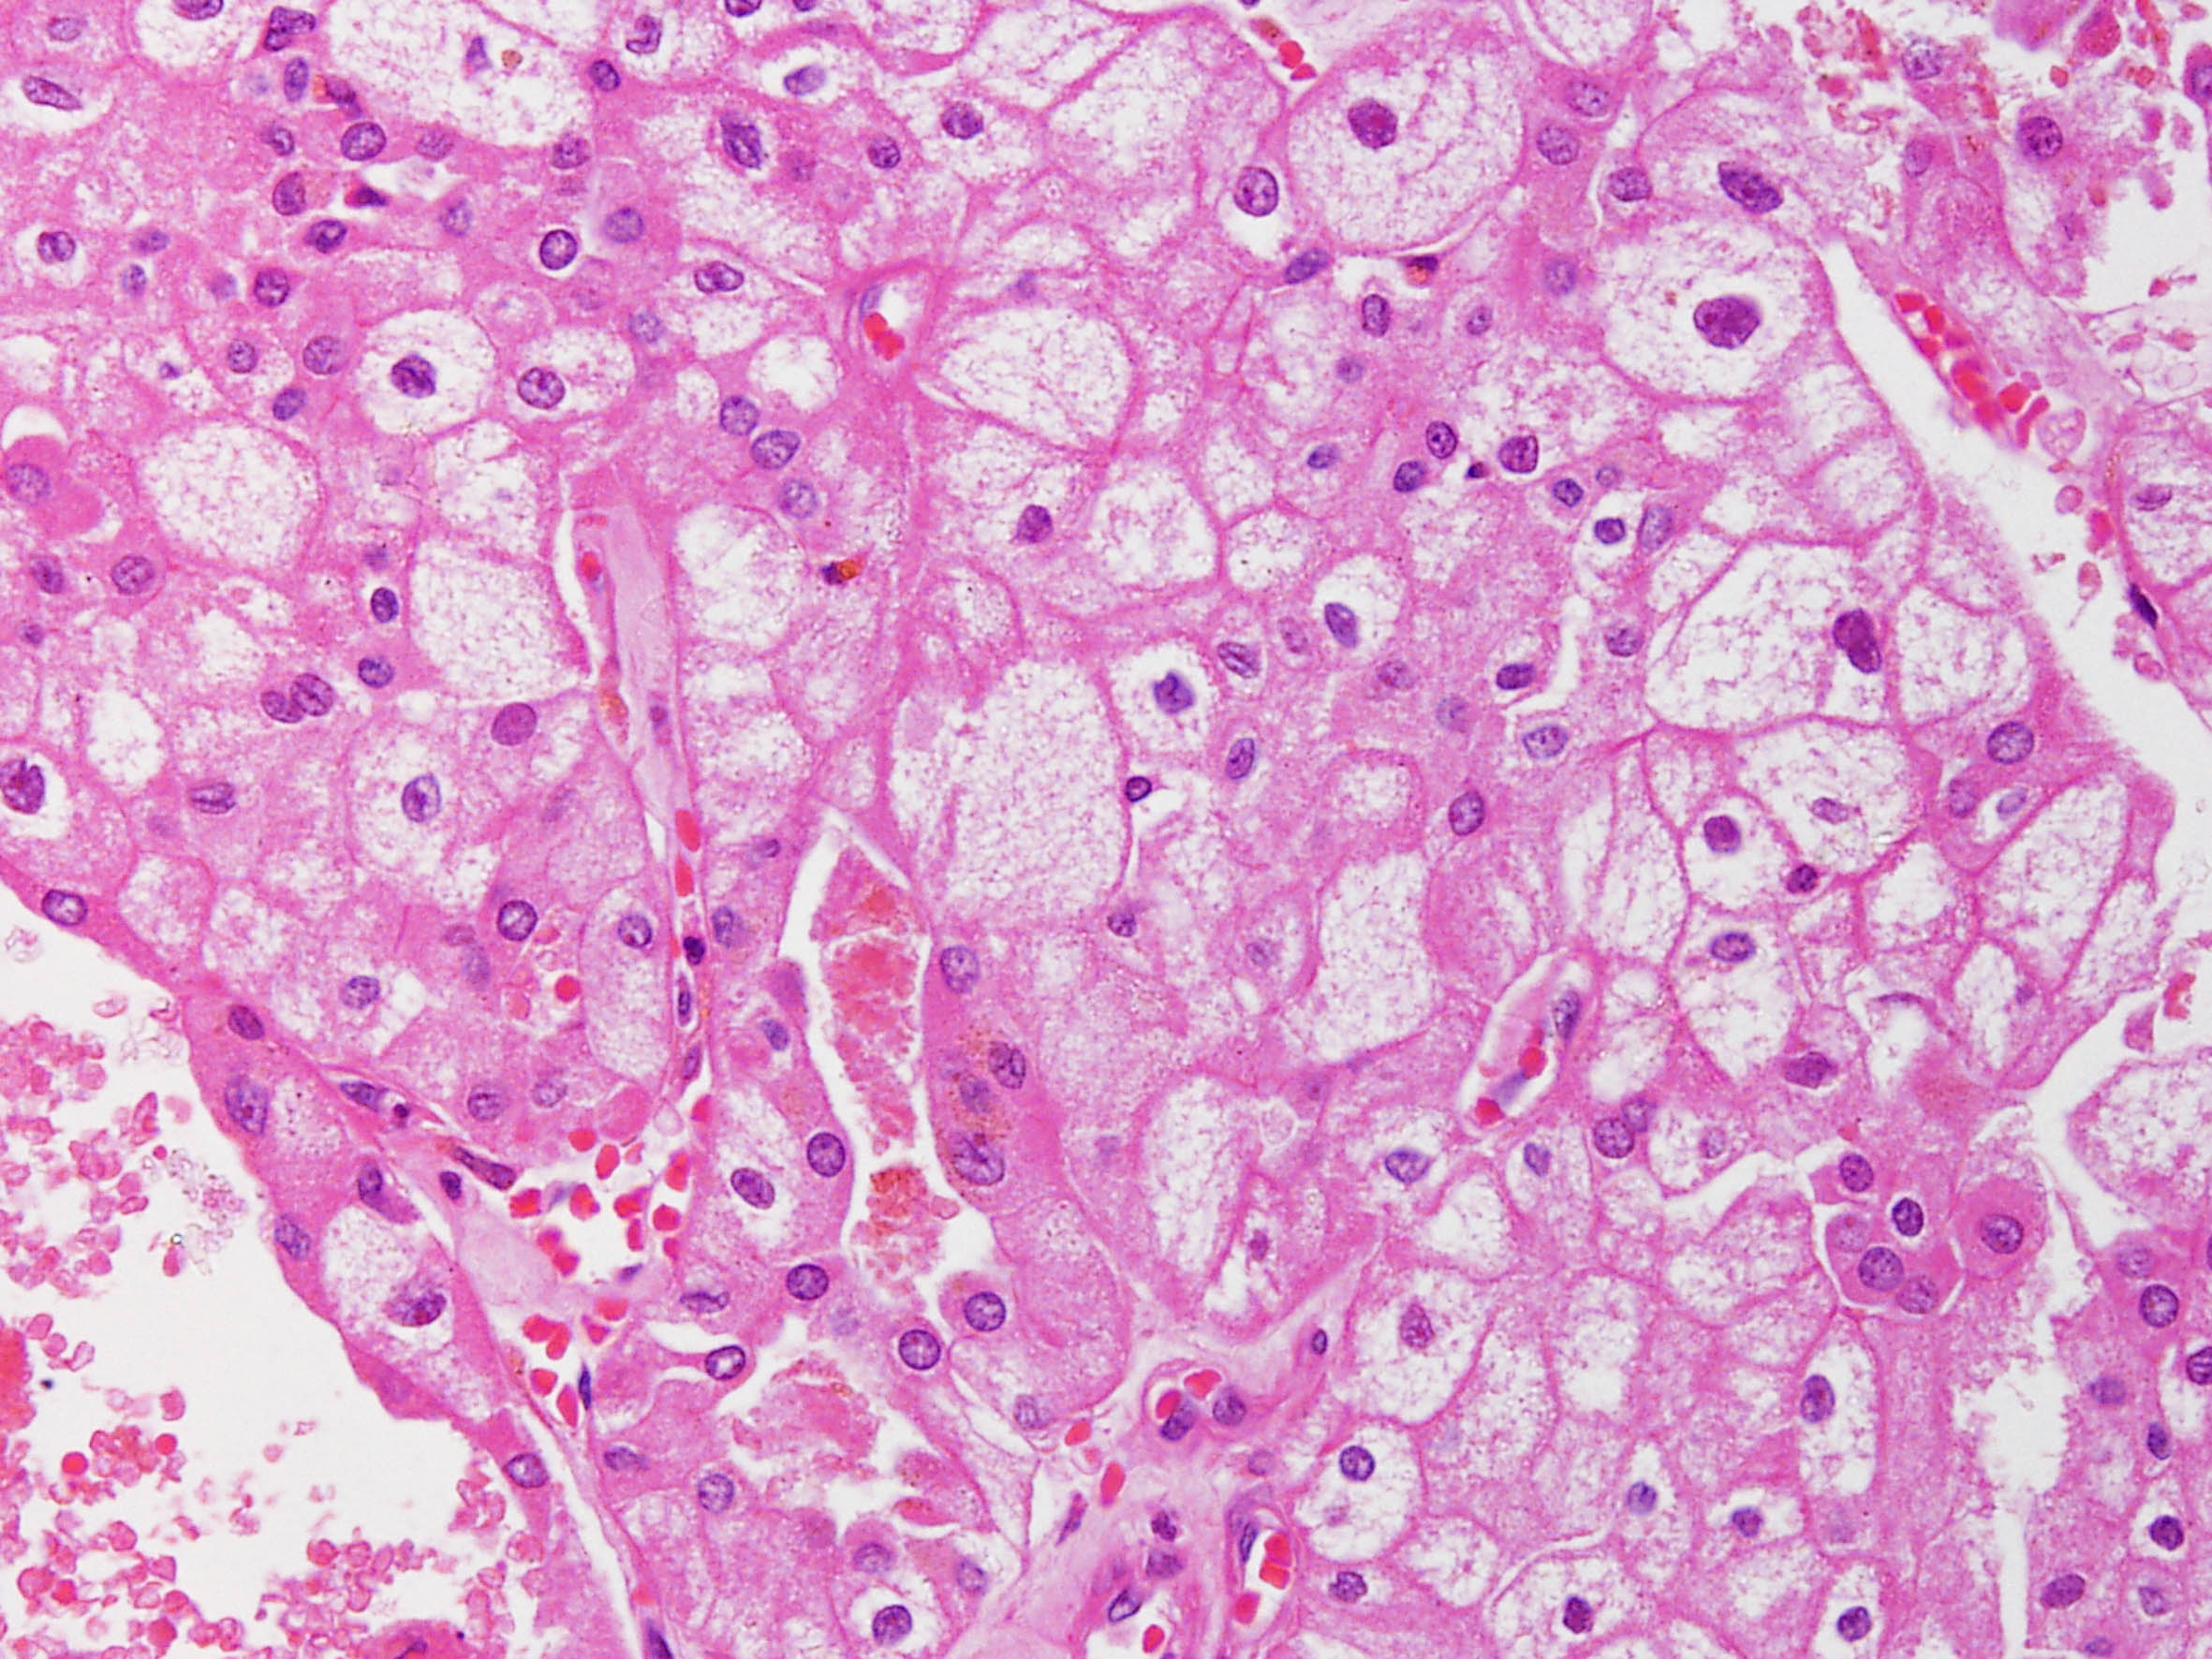

Chromophobe renal cell carcinoma